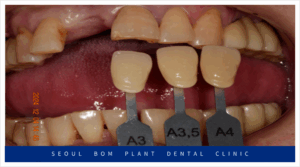

양측 위아래 어금니의

임플란트 보철물이 마무리되고 나서

앞니 심미보철치료를 진행하였는데요.

앞니는 심미성이 중요한

부위이다 보니 치아를 다듬기 전

환자분과 함께 색상과 모양을

꼼꼼하게 확인하는 작업을 거쳤으며

보철물 수복에

필요한 만큼의 양만 삭제하여

신경치료 없이 진행을 하였습니다.

앞니도 어금니와 마찬가지로

심미성이 높은 지르코니아

보철물로 수복해 드리면서

모든 치료를 마무리해 드렸는데요.

환자분께서는 임플란트를

사용하실 때보다

훨씬 더 심미적여서

마음에 드신다고 말씀해 주셨으며,

양측 어금니의 식사가 가능해져

만족해 하셨는데요.